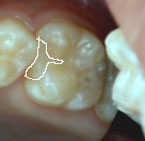

実際の写真をご覧ください。

右上の第一大臼歯 |

どちらも歯と歯の間に出来たむし歯部分を取り除き、詰めたものです。

白い線で囲んだ部分がレジンです。

左の写真のレジン充填は溝の部分を削らず、

シーラントをしてあります。

レジンもシーラントもプラスチックなのでそれが可能です。

インレーは金属なので溝だけシーラントをすることはできず、

従って右の写真のように大きく歯を削ることになるのです。 |